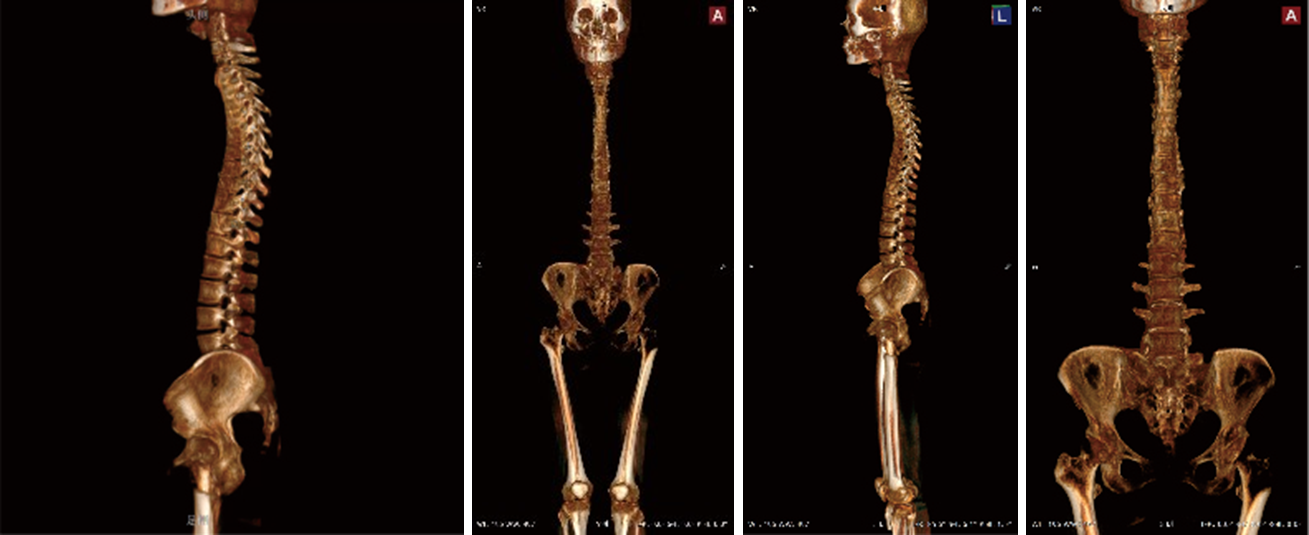

VR (Volumen-Rendering)

Durch die Computer-Rendering-Technologie WR-3D kann VR (Volume Rendering) durchgeführt werden, was Ärzten eine intuitivere Diagnose ermöglicht.